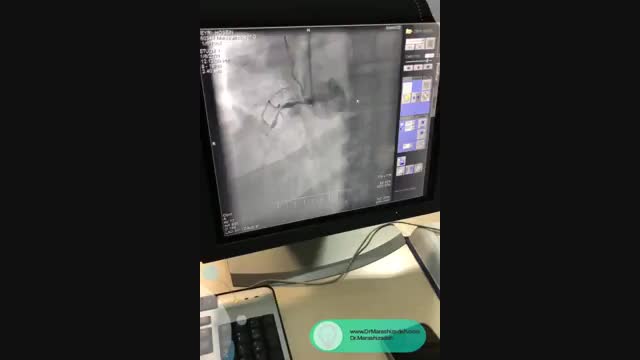

فیلم بالا آنژیوگرافی بیمار 54 ساله ای است که به علت درد قفسه سینه مراجعه کرده اند و سی تی آنژیو برای ایشان انجام شده است.